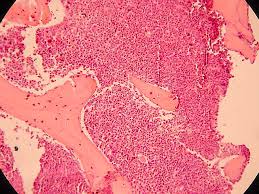

Leucemia melodie cronica: un nome che spaventa, una patologia seria e grave per la quale oggi è stata presentata una importante novità. Un nuovo farmaco, la molecola bosutinib è in grado di ridurre la mortalità per la malattia e si è dimostrato capace di ridurre notevolmente lo sviluppo di nuove cellule leucemiche. I dati sono stati presentati durante il congresso della Societa’ americana di ematologia (Ash) in corso ad Orlando (Usa), ma vengono dal nostro paese, in particolare dal dipartimento di Medicina clinica dell’Università Bicocca di Milano e dall’Unità di Ematologia dell’Ospedale San Gerardo di Monza. Contro una delle più gravi forme di leucemia, la leucemia mieloide cronica (LMC), l’obiettivo di una vittoria completa non è più un miraggio: dopo l’avvento di imatinib (Glivec), la terapia mirata in grado di assicurare percentuali di sopravvivenza di circa il 90 per cento, il Comitato scientifico dell’EMEA (CHMP) ha raccomandato nei giorni scorsi l’approvazione di Tasigna (nilotinib), nuovo farmaco Novartis destinato a trattare il piccolo numero di pazienti che manifestano resistenza o intolleranza al Glivec.

Il via libera europeo è stato annunciato a Bologna, “Nilotinib rappresenta un importante passo in avanti nella terapia della leucemia mieloide cronica, in quanto si è dimostrato un valido presidio terapeutico per i non molti pazienti che sono andati incontro a fallimento con imatinib”, afferma Michele Baccarani, Direttore Istituto di Ematologia e Oncologia Medica “L. e A. Seràgnoli” di Bologna. “Questa notizia conferma il momento positivo delle terapie contro i tumori del sangue, che possono avvalersi di farmaci sempre più efficaci e mirati. La ricerca in ematologia sta conoscendo una serie di successi che hanno radicalmente modificato le prospettive di molte malattie del sangue dando ai pazienti possibilità di sopravvivenza e a volte guarigione fino a qualche anno fa del tutrto impensabili”, ha affermato Sergio Amadori, Presidente Società italiana di Ematologia, direttore della Struttura Complessa di Ematologia del Policlinico Universitario Tor Vergata di Roma. L’avvento di nilotinib consolida la svolta inaugurata da Glivec, il farmaco che ha rivoluzionato la terapia dei tumori del sangue, grazie alla sua capacità di colpire selettivamente le cellule malate, risparmiando quelle sane. “Il Glivec è tuttora il farmaco di riferimento di questa patologia in quanto combina un risultato terapeutico da record – con una percentuale di sopravvivenza a 5 anni pari all’89 per cento – con effetti collaterali che oramai conosciamo e riusciamo in larga misura a controllare”, afferma Giuseppe Saglio, Direttore Medicina Interna 2 ed Ematologia, Dipartimento di Scienze Cliniche e Biologiche, Ospedale San Luigi Gonzaga, Università di Torino. Tuttavia, nonostante gli ottimi risultati che si ottengono nella maggior parte dei pazienti trattati con Glivec, in alcuni casi può però verificarsi un fallimento terapeutico, a causa della comparsa di resistenza o intolleranza al trattamento. Il fenomeno coinvolge solo una piccola parte dei pazienti, circa il 10 per cento di quelli trattati. Per offrire anche a loro una opportunità di cura, la ricerca ha messo a punto nilotinib, un inibitore della tirosin chinasi BCR-ABL di seconda generazione, dotato di una maggiore selettività e potenza, caratteristiche che si traducono in una rapida risposta clinica nei pazienti che per ragioni diverse possono non rispondere più a imatinib. Niilotinib riesce ad agire su 31 delle 32 mutazioni delle proteina che causano la leucemia mielodie cronica. Sono proprio queste mutazioni all’origine delle resistenze a imatinib. L’efficacia clinica di nilotinib in pazienti affetti da LMC Ph+ in fase cronica (CP) e accelerata (AP), è stata dimostrata in uno studio di fase II, che ha incluso oltre 500 pazienti. Tale studio ha coinvolto 15 dei principali centri di ematologia italiana, oltre che lo stesso Gruppo GIMEMA (Gruppo Italiano Malattie Ematologiche dell’Adulto), che hanno contribuito in maniera decisiva alla riuscita dello studio arruolando ben 118 pazienti (circa 27% della casistica totale). I due terzi dei pazienti con LMC-CP ha risposto alla terapia e nella maggior parte dei casi la risposta è stata raggiunta rapidamente: addirittura entro 3 mesi dall’inizio del trattamento con nilotinib (mediana 2.8 mesi). La percentuale di risposta complessiva per i pazienti con LMC-AP (fase acuta) è stata del 42 per cento e anche in questo caso la maggior parte dei pazienti ha raggiunto la risposta precocemente (entro 1-2 mesi dall’inizio del trattamento). I risultati ottenuti con nilotinib indicano che il farmaco è dotato di un’elevata efficacia in tale popolazione a rischio di progressione di malattia. Alla luce dell’importanza clinica di questi risultati, che aprono una possibilità di cura per pazienti che per ragioni diverse non rispondono più e che quindi andrebbero incontro a progressione, come già avvenuto per Glivec, nilotinib ha ottenuto l’approvazione da parte del Comitato scientifico dell’EMEA (CHMP) con procedura d’urgenza. Con questo nuovo farmaco lo spettro di efficacia delle attuali terapie contro la leucemia mieloide cronica si allarga. L’impegno di Novartis è adesso rivolto a trovare nuove soluzioni terapeutiche in grado di ridurre al minimo i casi di resistenza. Nella pipeline di Novartis sono in fase iniziale di sviluppo altre molecole, basate su un meccanismo d’azione diverso rispetto agli inibitori delle tirosin-chinasi, che nei prossimi anni potrebbero assicurare copertura terapeutica a un numero di pazienti sempre maggiore